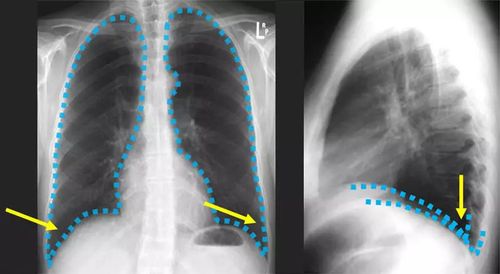

液平面x线图片,气液平面x线图片

气液平面x线图片

液气胸的x线图片

气胸x线胸片图解

胸腔积液x线胸片图解